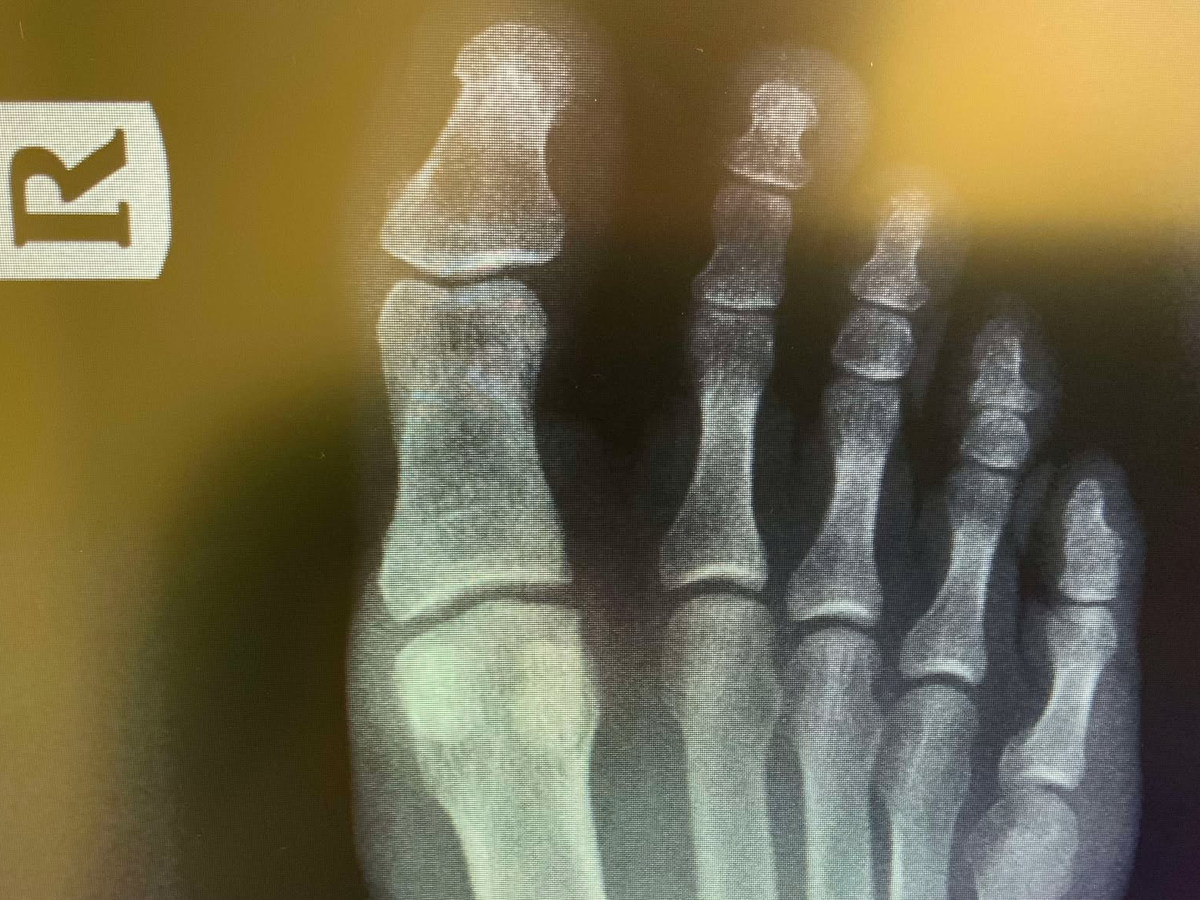

I'm an author and journalist with an amazing family and a small desert ranch in Southern California. I love our little hobby farm, but unfortunately it was one of our 250-lb goats that stepped on me almost nine months ago and broke a small bone in my right foot. My surgeon informed me that it hasn't healed, and that it won't heal, so he needs to remove the bone itself to keep the pain from lasting my entire life (fortunately, as he says, this bone is the tonsils of the toes, in that it is removable without ruining my ability to walk long term). I actually have health insurance, but the surgery is $18,000, and my plan only covers $10,000 of that. I'm expected to pay $8,000 up front at the time of surgery, which is in 10 days, and there are also special shoes and inserts, etc., I will need for recovery. In total, my share of the costs will be around $12,000. With the cost of maintaining about 100 total rescue animals on our ranch, I know I can't do that alone. I'm really hoping some of you out there are willing to chip in and make this a little easier. I sincerely appreciate all of you who read this, and those who contribute have my undying gratitude. Thank you all.